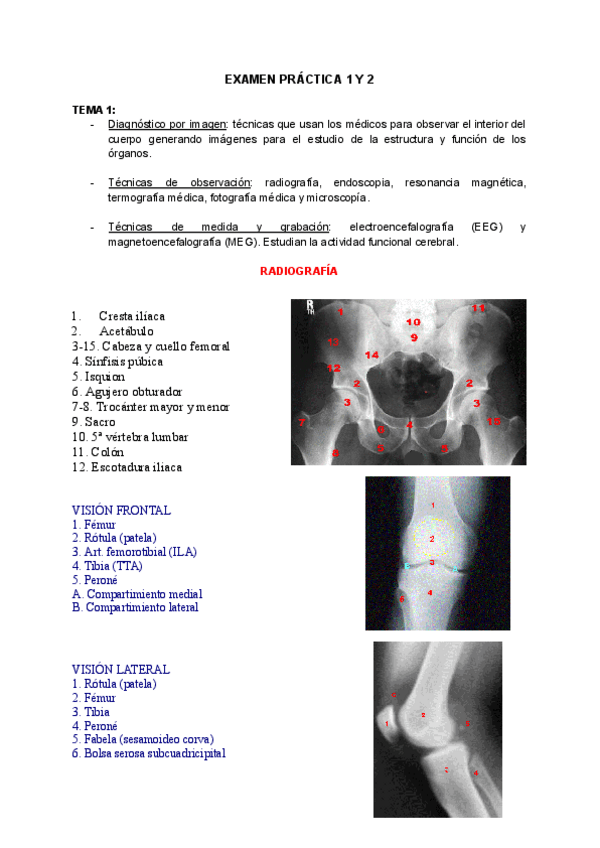

He publicado nuevos apuntes de 1º ANATOMÍA PARA LA ACTIVIDAD FÍSICA Y EL EJERCICIO: RESUMEN-PRACTICA-1-Y-2-ANATOMIA.pdf